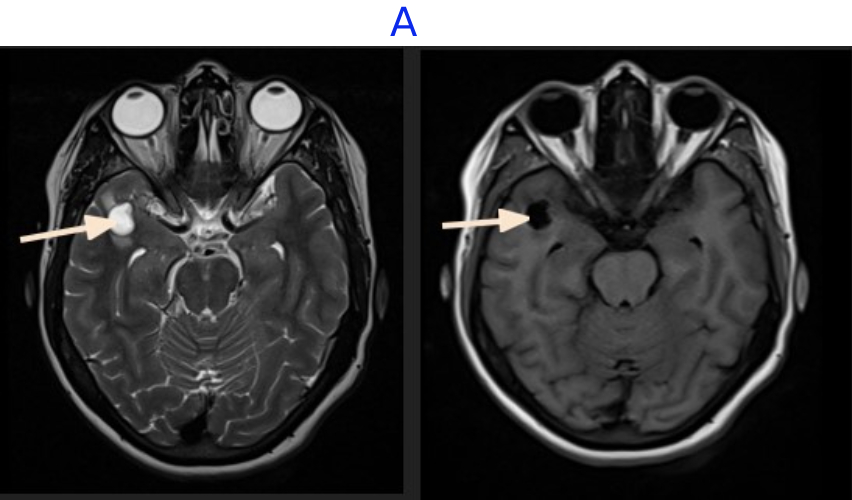

A. FINDINGS - MR BRAIN

• A. A well-defined, intra-axial, T2 hyperintense, T1 hypointense lesion measuring 14 x 12 x 9mm noted in the subcortical white matter of the peri-Sylvian right anterior temporal lobe